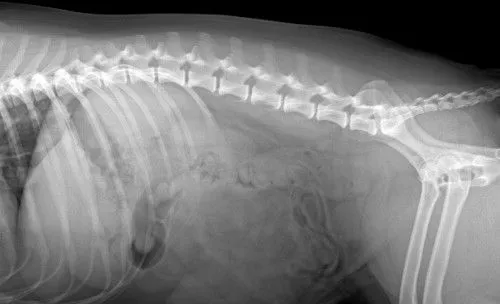

Before Surgery (arrow shows stones)